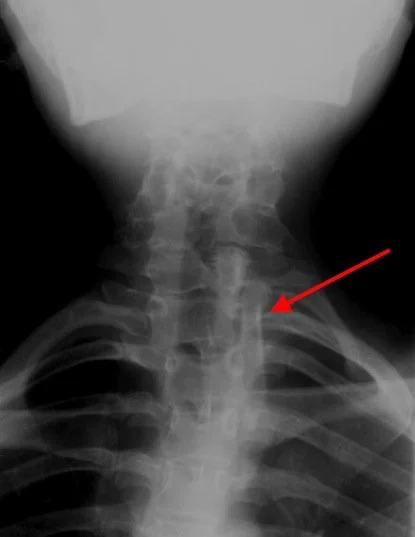

Left:

• Multilevel cervical fusion shown well

Right:

• Demonstrates left sided omnovertebral bone adjacent to C7-T3